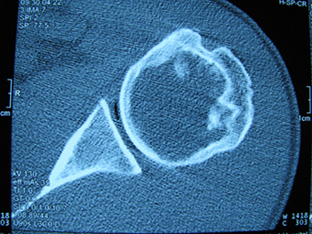

标题: X6404B:肱骨骨质破坏(CT片) [打印本页]

标题: X6404B:肱骨骨质破坏(CT片)

男,50岁,左肩部轻微疼痛,活动不便5个月就诊,近十天加重,无红肿热,间断理疗治疗无好转,既往5个月前左肩轻微拉伤史

骨巨?动脉瘤样骨囊肿?

内生软骨瘤。

内生软骨瘤。

内生软骨瘤?-----------

年纪大了,先要排除转移瘤。

髓腔内软组织肿块并斑片状钙化,考虑高分化软骨肉瘤可能性大。

考虑骨巨或动脉瘤样骨囊肿。

内生软骨瘤可能性大,期待结果。

孤立性骨囊肿。

内生软骨瘤可能性大

其内可见钙化,考虑软骨源性肿瘤,内生软骨瘤可能

但由于年龄较大,恶性软骨肉瘤待排

肱骨头内巨大软组织肿块并斑片状钙化,内生软骨瘤?骨巨细胞瘤?软骨粘液样纤维瘤?期待结果!

髓腔内软组织肿块并斑片状钙化,考虑高分化软骨肉瘤可能性大。

内生软骨瘤可能性大

肱骨头内巨大软组织肿块并斑片状钙化,内生软骨瘤?骨巨细胞瘤?软骨粘液样纤维瘤?期待结果

考虑内生软骨瘤?骨巨细胞瘤?

内生软骨瘤?骨巨细胞瘤?

先要排除转移瘤。